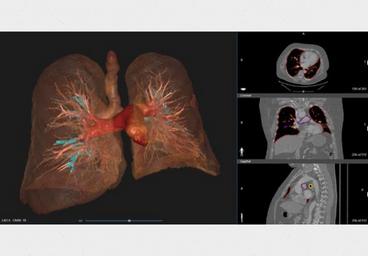

Experience the benefits of 3D printing in surgery with a personalized 3D printed model tailored to the patient's needs, assisting surgeons in achieving the best possible outcome for the surgery.

3D printing has revolutionized pre-surgical planning by providing doctors with accurate and detailed 3D models of patient anatomy. With 3D printing technology, doctors can now visualize complex structures and plan surgical procedures with greater accuracy and precision. This technology enables doctors to identify potential risks, explore different surgical options, and develop personalized treatment plans for each patient. 3D printing also helps to reduce surgery time and minimize the risk of complications, resulting in improved patient outcomes. With 3D printing, doctors can enhance their pre-surgical planning process, delivering better care to their patients.

While performing a surgical procedure, the stakes are high, and even a small error can have disastrous consequences. Therefore, it's crucial to be well-prepared for any unexpected challenges that may arise during the surgery. By taking the necessary precautions and having a detailed plan of action, surgeons can ensure the best possible outcome for their patients. In the world of life and death, preparedness is the key to success.

Our state-of-the-art surgical preparation service includes the use of advanced technology such as

3D printing to provide surgeons with accurate and detailed anatomical models. By using patient-specific

CT and MRI scans to create these models, surgeons can perform mock surgeries to plan and prepare for the

actual procedure. This process not only helps to avoid any potential surprises during surgery but also

boosts the surgeon's confidence and morale, knowing they have a comprehensive understanding of the

patient's anatomy. With our advanced preparation techniques, you can rest assured that your surgical

team is fully equipped to provide you with the best possible outcome.

Transforming surgical planning with customized 3D printed models, created from patient CT and MRI scans. Our cutting-edge 3D printing technologies, including FDM, SLS, and SLA, allow for precise and accurate replicas that provide invaluable preoperative and operative guidance for surgical teams. In addition, we provide virtual 3D models in multiple file formats, enabling further analysis and planning for optimal patient outcomes. Trust us to enhance your surgical precision and improve patient care with our advanced 3D printing solutions.

Revolutionize surgical precision with personalized 3D printed surgical guides, designed to minimize the risk of errors and ensure optimal accuracy. Our state-of-the-art 3D printing technologies, including FDM, SLS, and SLA, allow us to create customized surgical guides that fit each patient's unique anatomy and aid surgeons in achieving unparalleled precision, even in the absence of unexpected elements. Trust us to provide cutting-edge solutions that enhance your surgical outcomes and improve patient care.

Revolutionize surgical planning with real-time 3D virtual models, generated from patient CT and MRI scans. Our cutting-edge technology allows for visualization of the patient's case in real-time, providing invaluable insights for preoperative surgical planning. These 3D digital models can be exported in various file formats, enabling numerous applications for further analysis and planning. By improving the comfort and efficiency of your doctor/surgeon to comprehend and operate, our virtual 3D models enhance surgical precision and patient outcomes. Trust us to deliver innovative solutions that transform the way you approach surgery.